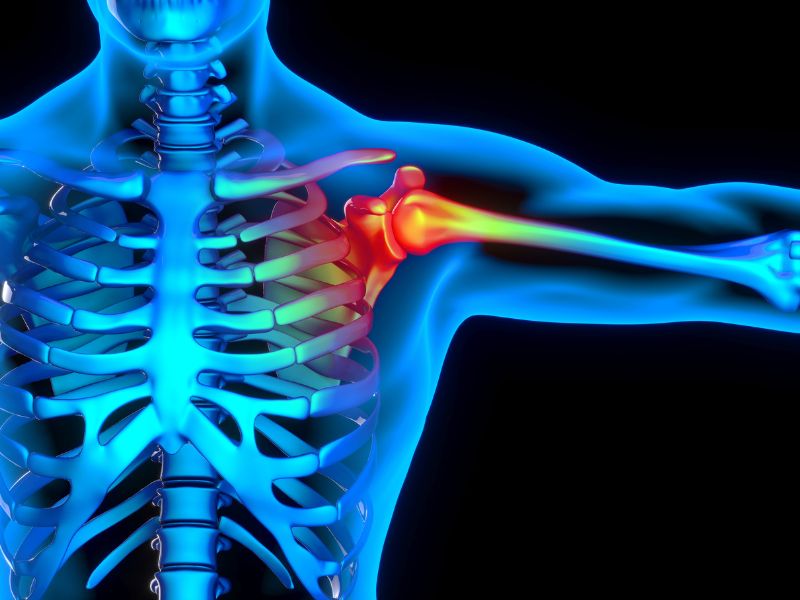

Schulterimpingement durch Würfe

- • Arthroskopie in Spezialklinik